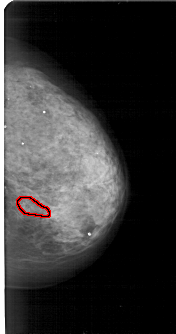

A_1810_1.RIGHT_CC

RIGHT_CC LINES 4996 PIXELS_PER_LINE 2626 BITS_PER_PIXEL 12 RESOLUTION 43.5 OVERLAY

FILE: A_1810_1.RIGHT_CC.OVERLAY

TOTAL_ABNORMALITIES 1

ABNORMALITY 1

LESION_TYPE CALCIFICATION TYPE PLEOMORPHIC DISTRIBUTION CLUSTERED

ASSESSMENT 4

SUBTLETY 2

PATHOLOGY BENIGN

TOTAL_OUTLINES 1

BOUNDARY